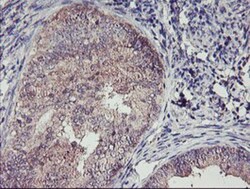

| Antigen | TMEFF2/Tomoregulin-2 |

| Applications | Western Blot, Immunohistochemistry, Immunohistochemistry (Paraffin) |

| Dilution | Western Blot 1:500-2000, Immunohistochemistry 1:150, Immunohistochemistry-Paraffin 1:150 |